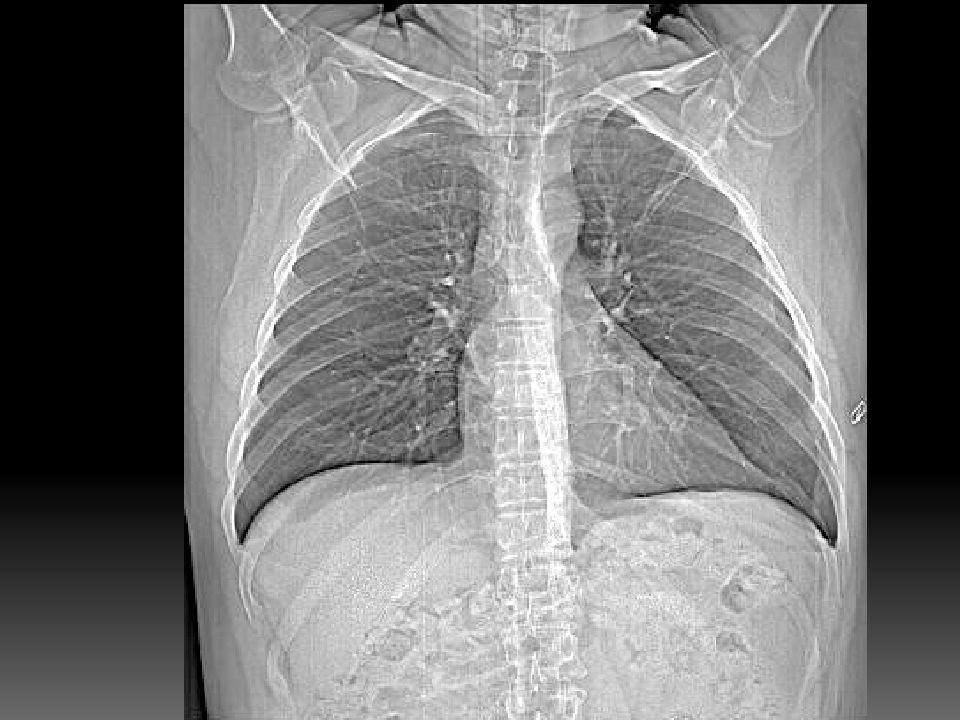

Рентгеновские технологии: усиленные экраны 35x35